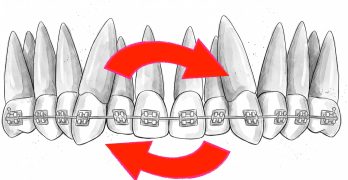

Brackets Damon Ultima y Protocolo de Bite Turbos y Elásticos en una Clase II Severa

Hoy traemos un artículo del Journal of Digital Orthodontics llamado Management of Anterior Deep Bite and Posterior … [Leer más...] acerca de Brackets Damon Ultima y Protocolo de Bite Turbos y Elásticos en una Clase II Severa